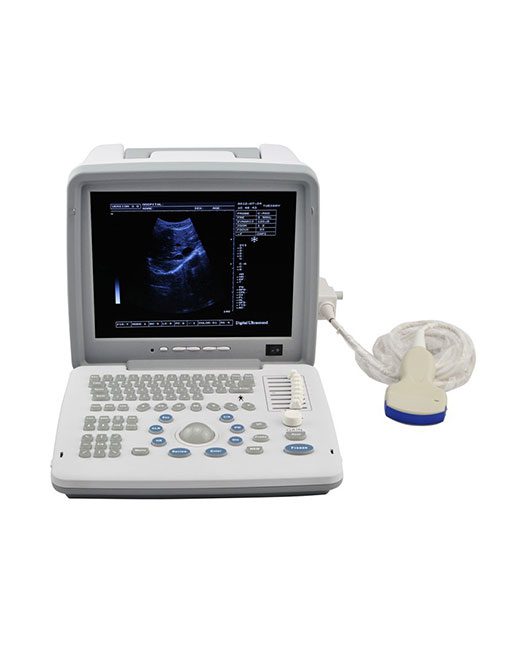

XF300 (LED) B ultrasound diagnose medical instrument

Portable LED screen ultrasound

XF300 (LED) B ultrasound diagnose medical instrument

The fully digital ultrasound image diagnostic equipment,

12in LCD screen main unit with one probe |

Real photos